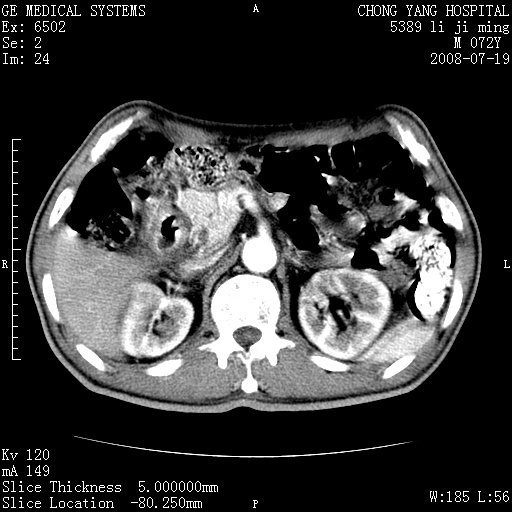

以下是引用zjzjr在2008-7-19 20:57:00的发言:[br]胰头增大,边缘模糊,周围可见渗出影,右侧肾前筋膜增厚.支持胰腺炎.

以下是引用yangyudong333在2008-7-20 6:56:00的发言:[br]胰腺增大尤以胰头明显,边缘模糊,周围可见渗出影,右侧肾前筋膜增厚,肠管於涨.支持胰腺炎

以下是引用不学无术在2008-7-19 23:15:00的发言:[br]胰腺增大尤以胰头明显,边缘模糊,周围可见渗出影,右侧肾前筋膜增厚,肠管於涨.支持胰腺炎